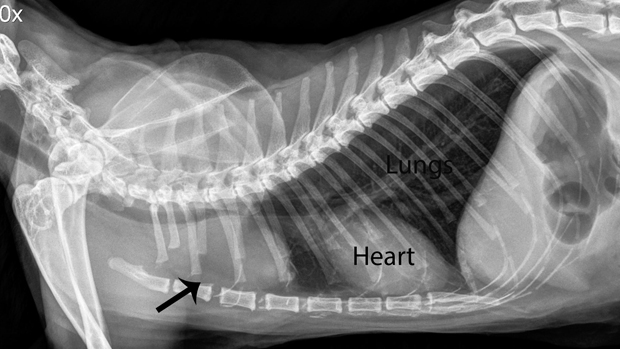

This is the radiograph of an older pet that seemed fine at home except for the fact it was listless. A chest radiograph revealed a large mass (at the arrow) causing the problem. This would not have been detected without the radiograph, a very important diagnostic tool on our patients that cannot tell us how they feel.